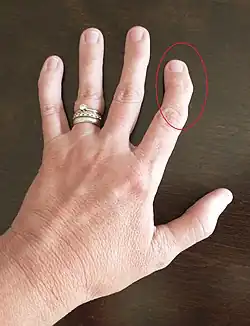

Swan-neck deformity is depicted by difficulty in finger bending, finger deformity, and stiffness.[10] Rheumatoid arthritis is a primary cause of swan-neck deformity due to the presence of inflammation of the joints.[11] Additionally, swan-neck deformity can be caused by weakening or tearing of the ligament and tendon on the middle joint of a finger.[10] Other causes of swan-neck deformity include untreated mallet finger, muscle spasticity, physical hand trauma, and many others.[11]

Trauma deformities may manifest as reduced joint function due to lack of coordination in phalangeal joints, such as proximal interphalangeal flexion and distal interphalangeal hyperextension in boutonnière deformity.[1] Besides trauma, another reason boutonnière deformity may develop is due to a chronic disease like rheumatoid arthritis.[1] Gamekeeper's thumb can also be provoked by either sport related trauma, or excessive use.[4] With some trauma deformities, macroscopically, certain digits may be unable to straighten.[1] With gamekeeper's thumb, where the ulnar collateral ligament (UCL) is damaged, thumb functional abilities may be diminished.[4] For fingertip deformities, such as in mallet finger, pain and fingernail disruption may also be observed.[13]

Deformities possibly instigated by chronic events can involve but are not limited to Dupuytren's contracture [3] and swan-neck deformity.[20]

Many of these deformities, such as Dupuytren's contracture, swan-neck deformity etc. can be associated with both a chronic, progressive event, or an acute injury;[17] such as boutonnière deformity, which can be caused by trauma,[1] or induced by a chronic condition like rheumatoid arthritis.[20] The causes of some deformities, such as Dupuytren's contracture, are difficult to determine exactly, however chances of developing the deformity may be increased by certain chronic behaviours or disease.[3]

Consequences can be similar to trauma related ones, in that joint use may be disrupted.[20] However, what differentiates these is their cause; a chronic onset rather than being due to an acute event.[20] Certain treatments can reduce their severity.[20]